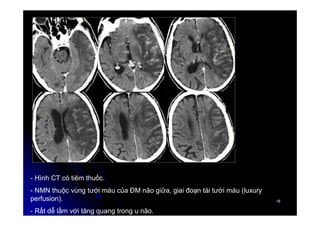

- Hình CT có tiêm thuốc.

- NMN thuộc vùng tưới máu của ĐM não giữa, giai đoạn tái tưới máu (luxury

perfusion).

- Rất dễ lầm với tăng quang trong u não.